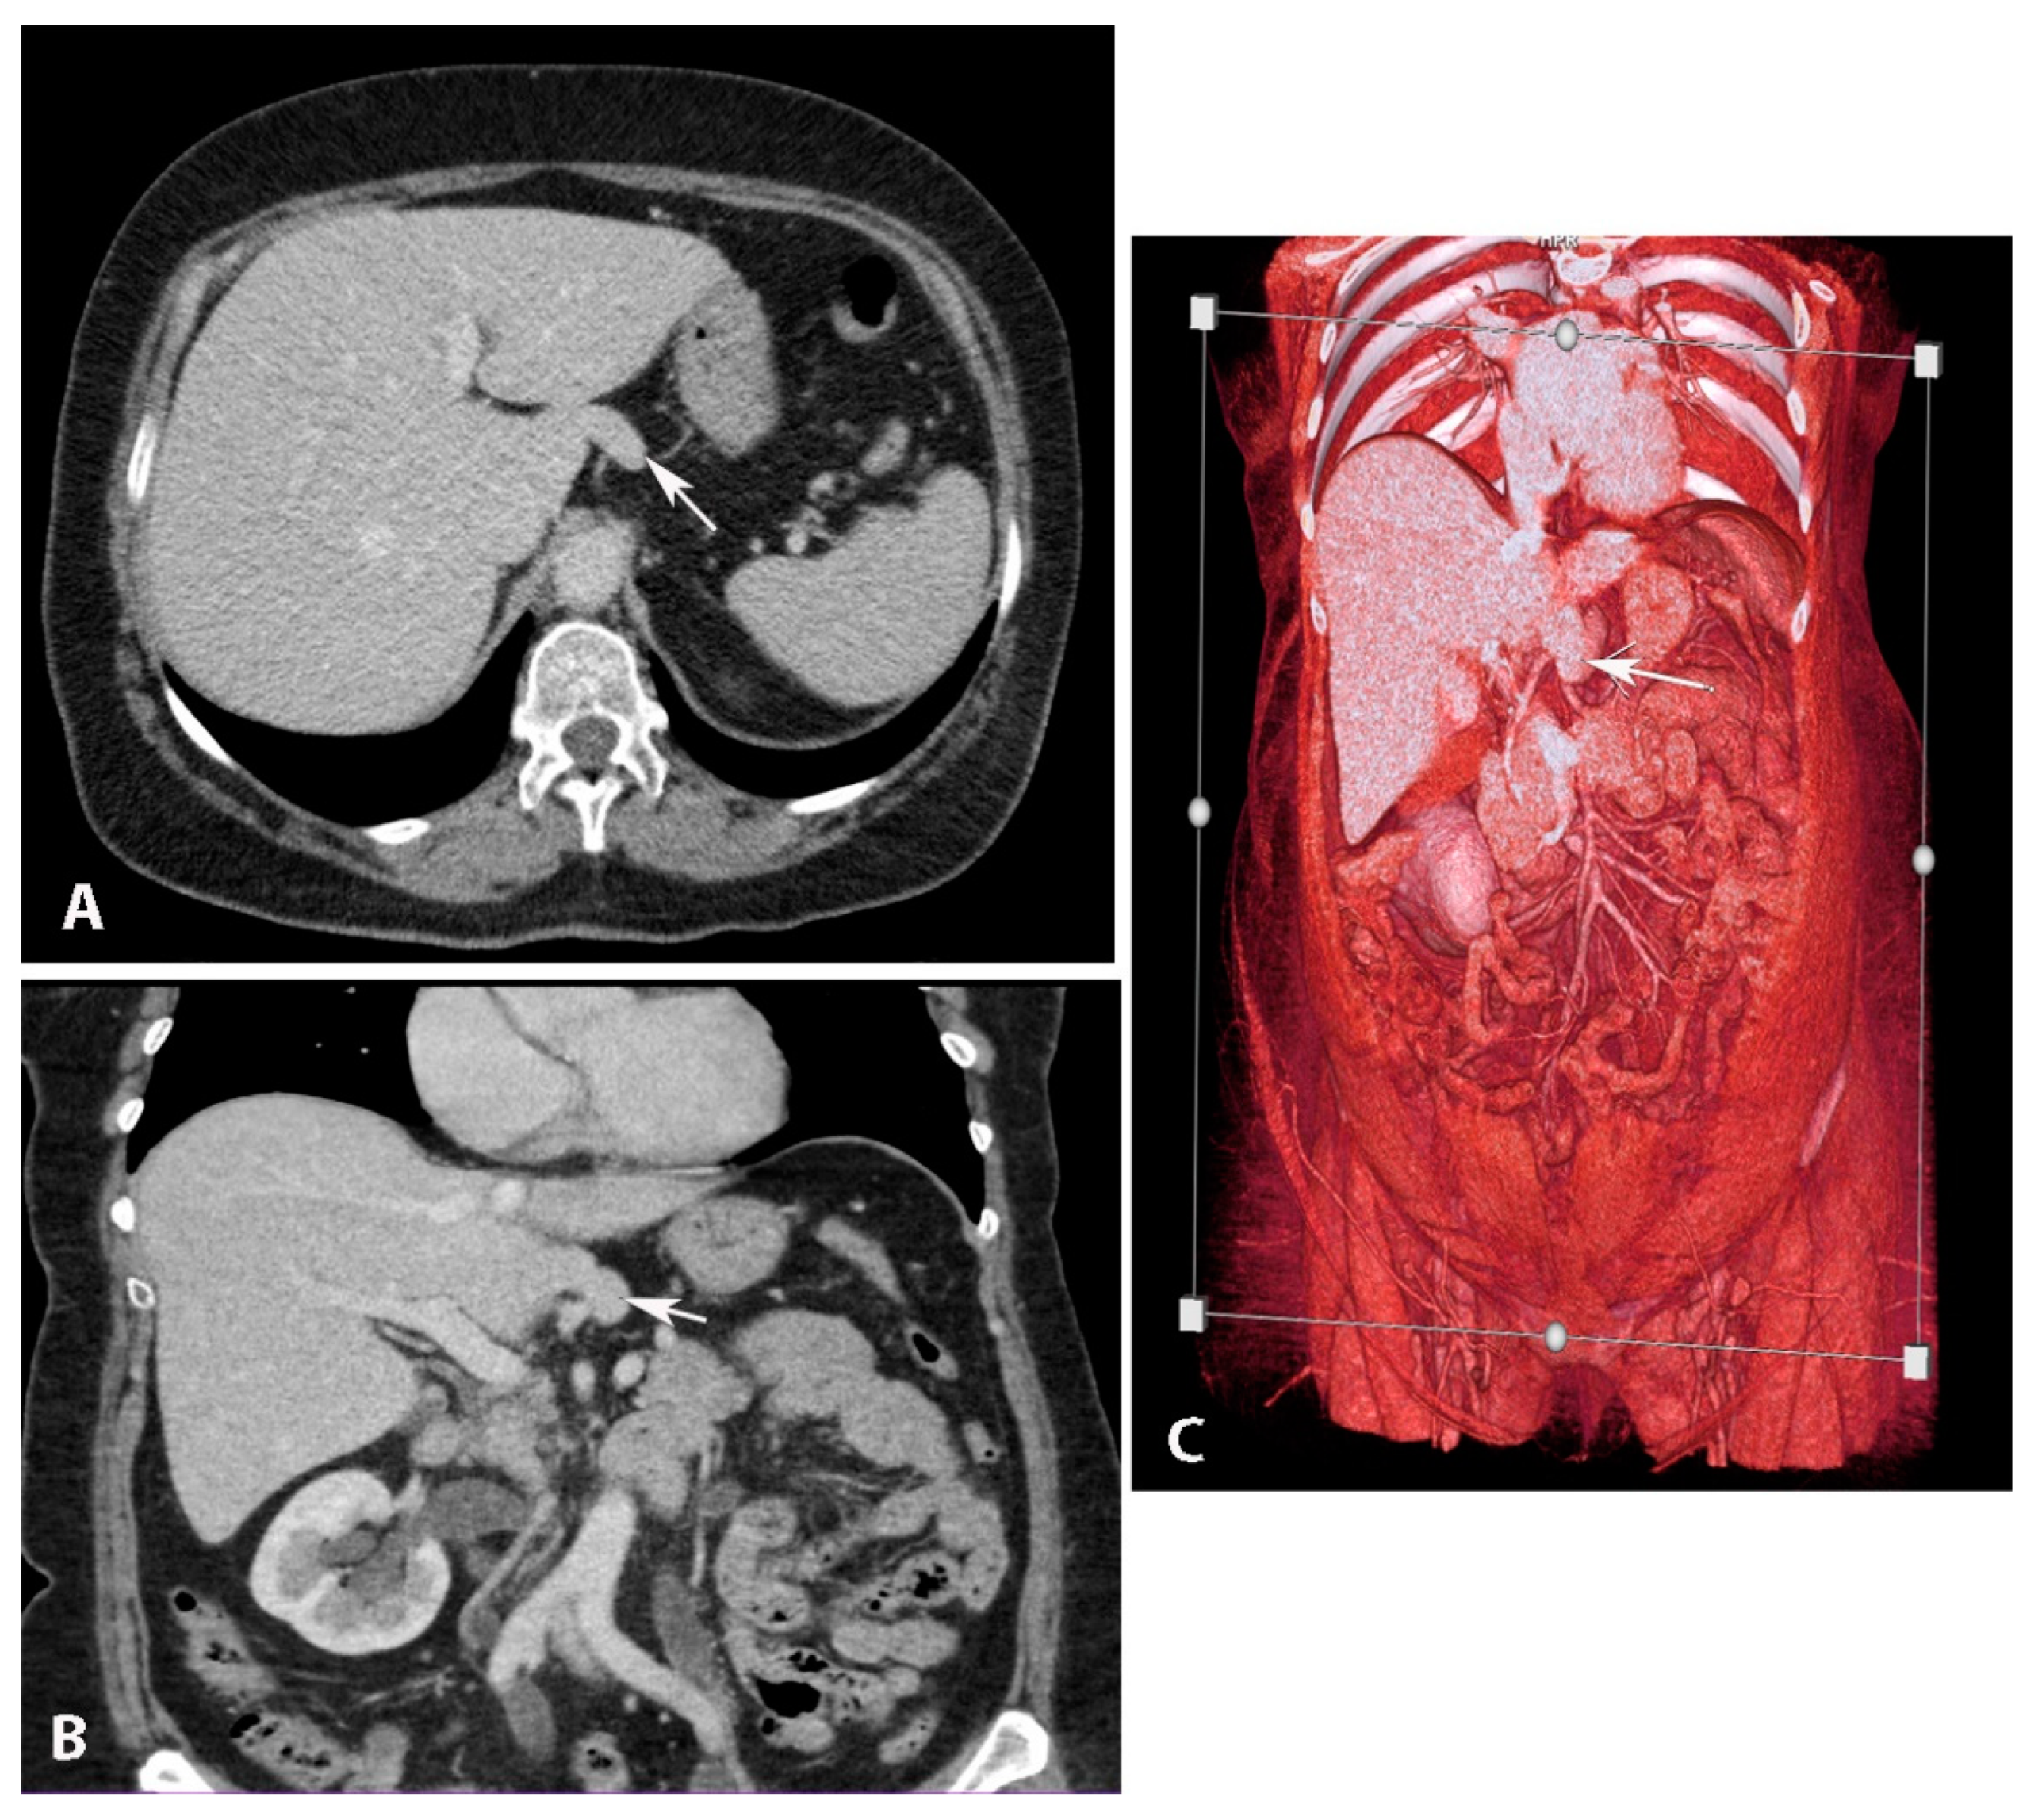

3.3. Riedel’s Lobe

Significance of Riedel’s Lobe in Ovarian Cancer Surgery